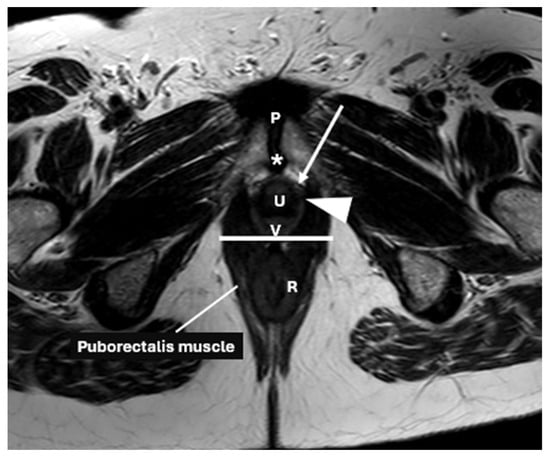

2. Anatomical Structure of the Pelvic Floor